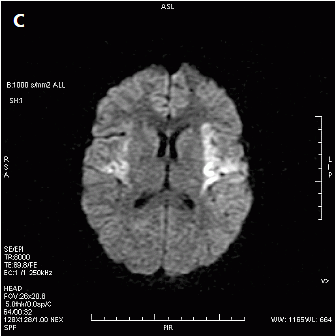

Na rentgenogramie przedstawione jest złamanie Saltera-Harrisa typu

Ilustracja do pytania 19

A. II odcinka bliższego kości piszczelowej.

B. V czwartej kości śródręcza.

C. I ześlizgnięcie bliższej nasady kości udowej lewej.

D. III nasady dalszej kości piszczelowej.